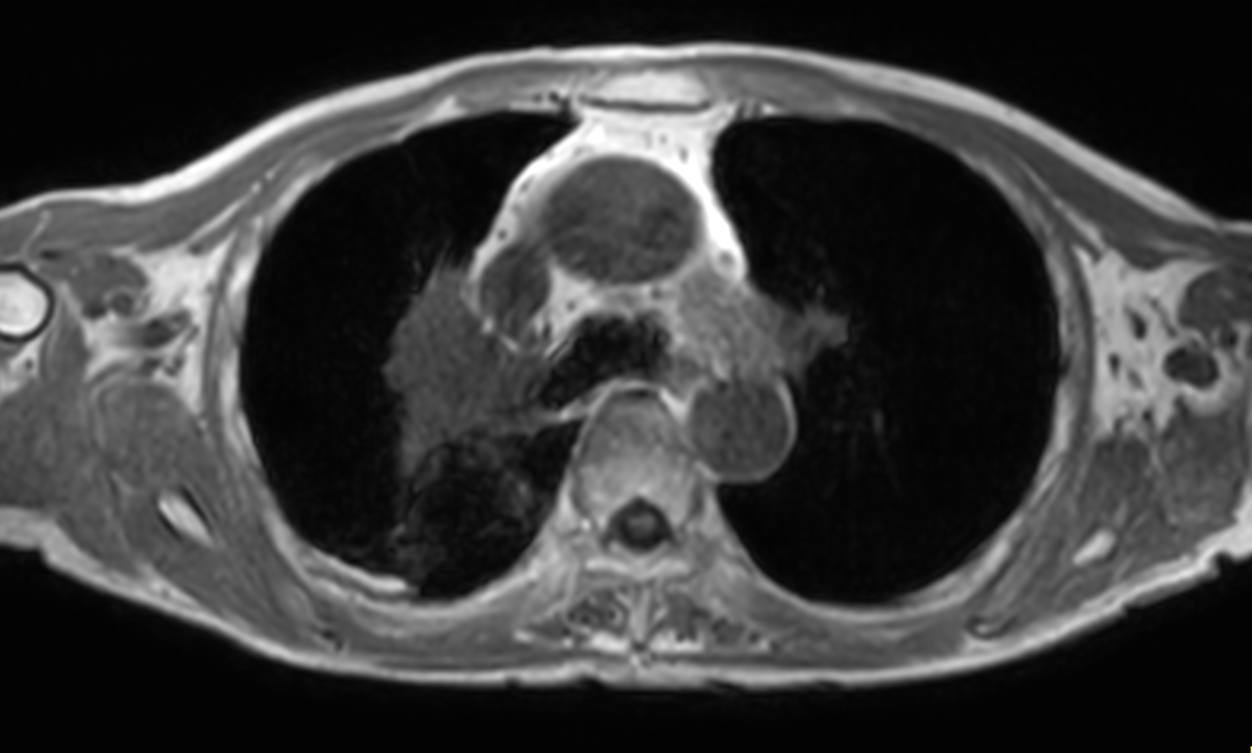

Patient with lung cancer. The ExamCard includes techniques for efficient fat-free imaging over large field-of-views (mDIXON XD), a diffusion procedure with less distortion (DWI TSE XD), a multi-phase contrast-enhanced sequence (4D FreeBreathing) to improve imaging confidence and Compressed SENSE to accelerate the entire exam.

T2w TSE